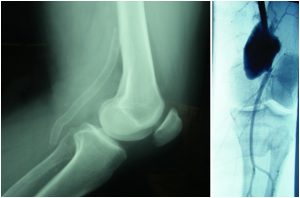

aneurisma-popliteo por admin | Ago 19, 2016 | 0 Comentarios Aneurisma popliteo: Reparación endovascular mediante Stent recubierto. Enviar comentario Cancelar la respuestaTu dirección de correo electrónico no será publicada. Los campos obligatorios están marcados con *Comentario * Nombre * Correo electrónico * Web Guarda mi nombre, correo electrónico y web en este navegador para la próxima vez que comente. Δ